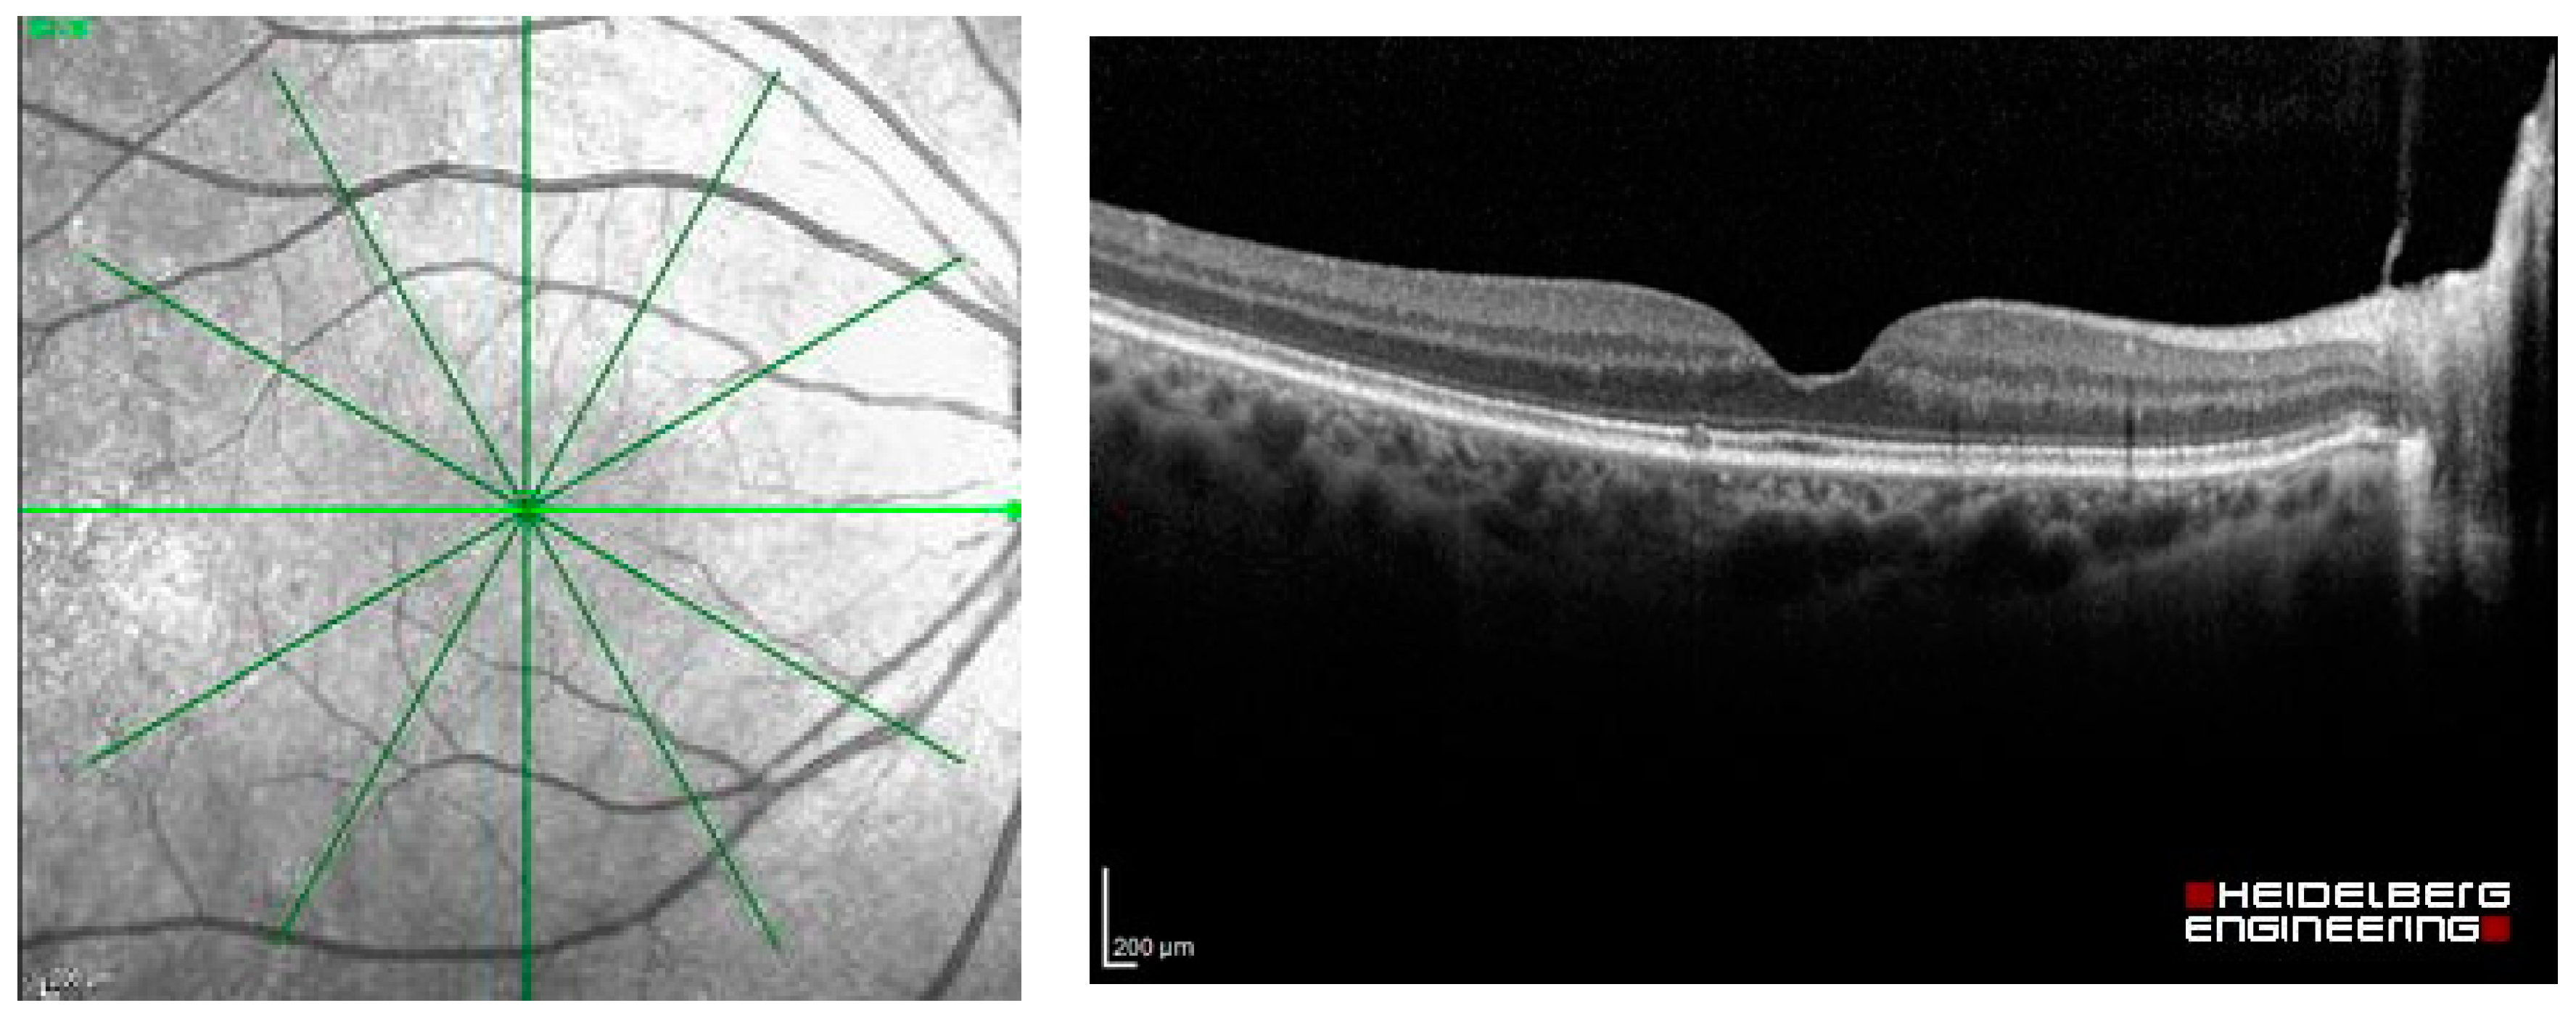

Figure 2.

Radial OCT scan of a retina and example of an OCT image of the light green line.